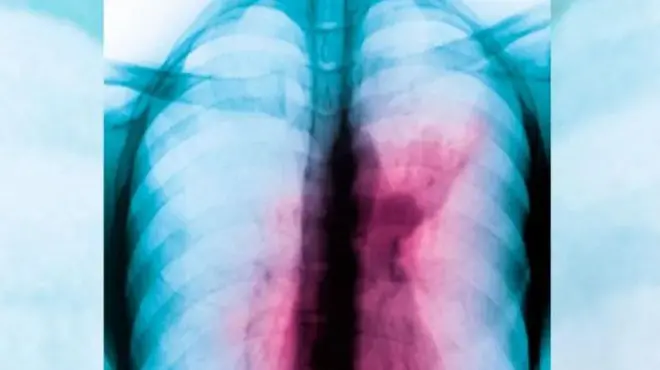

Dịka mbaụwa weere ubochị 24 nke ọnwa Maachị afọ ọbụla echeta ọrịa ụkwaranta, Janet Iyiola so na ụfọdụ ndị ji ọṅụ echeta ya bụ ụbọchị.

Janet dara ọrịa a gbagwojuru ya anya n'afọ 2009, ọ gara ụlọọgwụ ma gakwaa ebe ndị ọzọ mana ọ chọpụtaghi ihe na-arịa maọbụ nwete ọgwụgwụ.

Mgbe ọ gara, ha nyochara ya ahụ ma chọpụta na ọ bụ ọrịa ụkwaranta nke na-emetụta ọkpụkpụ azụ ka ọ na-arịa.